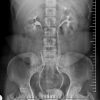

– Thận đôi (Duplex kidney): 2 đài bể thận riêng biệt thoát ra từ 1 thận.

– Đường bài xuất đôi (Duplex collecting system):

+ Niệu quản đôi (Double ureter): 2 đài bể thận với 2 niệu quản riêng biệt đổ vào bàng quang.

=> Hệ niệu đôi hoàn toàn: 2 đài bể thận và 2 niệu quản riêng biệt. Với hệ niệu đôi hoàn toàn, niệu quản dưới thường cắm vào bàng quang ở vị trí bình thường nhưng theo chiều vuông góc với thành bàng quang => làm cho niệu quản dưới hay bị trào ngược. Niệu quản trên cắm vào bàng quang ở vị trí thấp hơn và ở trong so với vị trí bình thường => đầu tận của niệu quản thường phồng lên trong lòng bàng quang tạo thành nang niệu quản với một miệng hẹp đổ vào lòng bàng quang